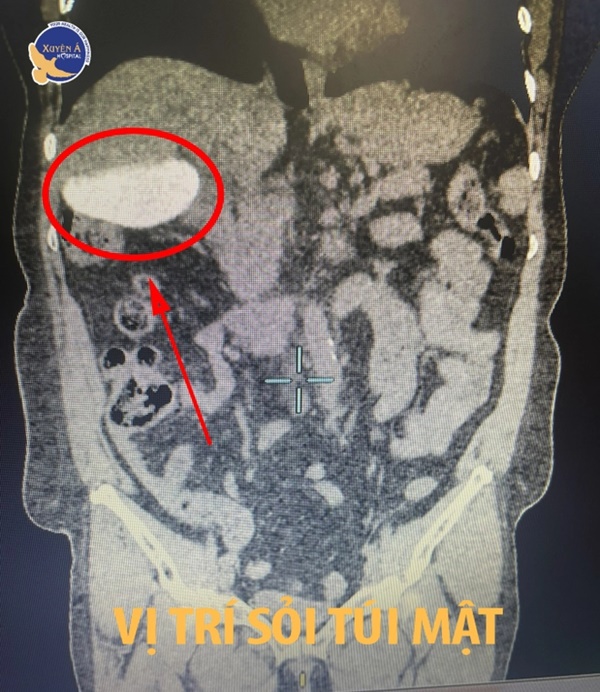

Ngay sau đó, bệnh nhân được chỉ định thực hiện các xét nghiệm cơ bản, chụp cắt lớp vi tính ổ bụng phát hiện gan xơ kèm sỏi lắp đầy túi mật. Bác sĩ đã thăm khám rất kỹ lưỡng trước mổ cho bệnh nhân và nhanh chóng tiến hành thực hiện nội soi cắt túi mật.

Túi mật chứa đầy sỏi của bệnh nhân được cắt bỏ thành công.